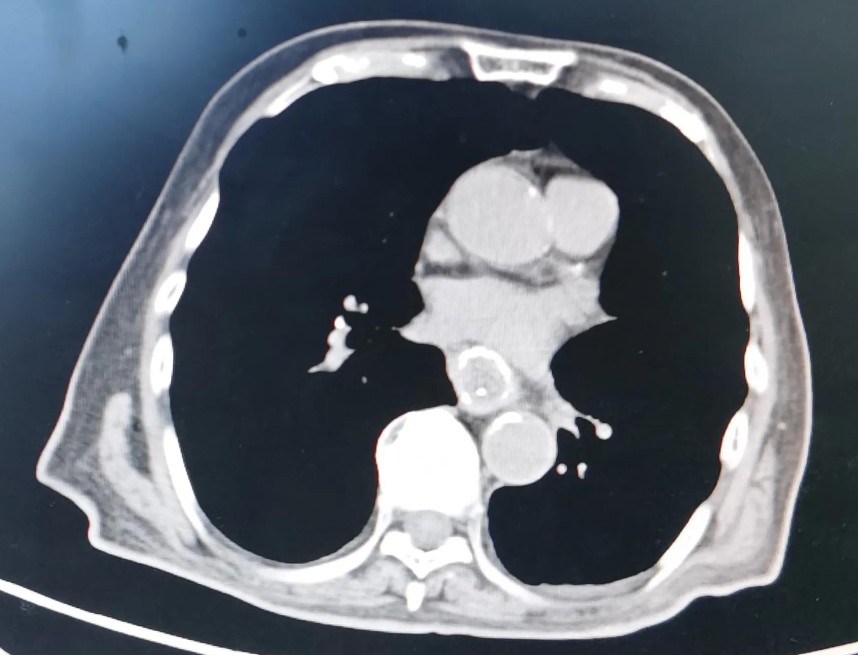

右肺部术后瘢痕

左侧股骨头置换

贲门部肿瘤CT表现